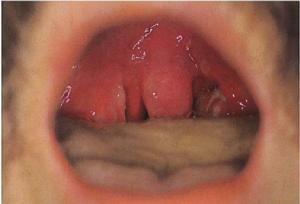

1、普通型

猩紅熱症狀疹間皮膚潮紅,用手壓可暫時轉白。面頰部潮紅無皮疹,而口周圍皮膚蒼白,稱口周蒼白圈。皮膚皺摺處,如腋窩、肘、腹股溝等處,皮疹密集,色深紅,其間有針尖大小之出血點,形成深紅色“帕氏”。口腔黏膜亦可見黏膜疹,充血或出血點。病程第1周末開始脫屑,是猩紅熱特徵性症狀之一,首見於面部,次及軀幹,然後到達肢體與手足掌。面部脫屑,軀幹和手足大片脫皮,呈手套、襪套狀。脫屑程度與皮疹輕重有關,一般2~4周脫淨,不留色素沉著。

丹痧2.中毒型起病急驟,體溫可高至40.5℃以上。全身中毒症狀明顯,頭痛、驚厥、嘔吐、為常見症狀。咽扁桃體炎症嚴重。有明顯紅斑疹。如合併膿毒症狀,甚至發生休克,危險性很高。

1.疑似病例發熱、咽痛,皮膚出現充血紅點疹或充血粟粒疹。

猩紅熱症狀(2)發熱1—2天內出疹,皮膚瀰漫性充血、潮紅,其間散布針尖大小猩紅色皮疹,壓之退色,2~5天后消退。